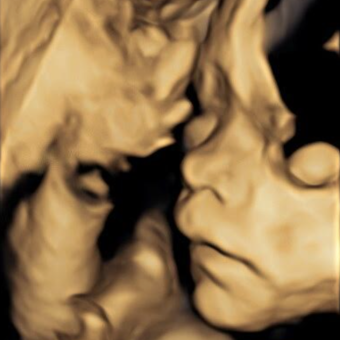

Jessica's Baby Registry

Jessica Perino & Kyle Hunderman

November 26, 2025

Thank you SO much for supporting us in this next big adventure! We are so grateful. We are totally open to used items, and books, meals, and hugs. We love our people, and are so excited for you to be our village (in this new, different way!).